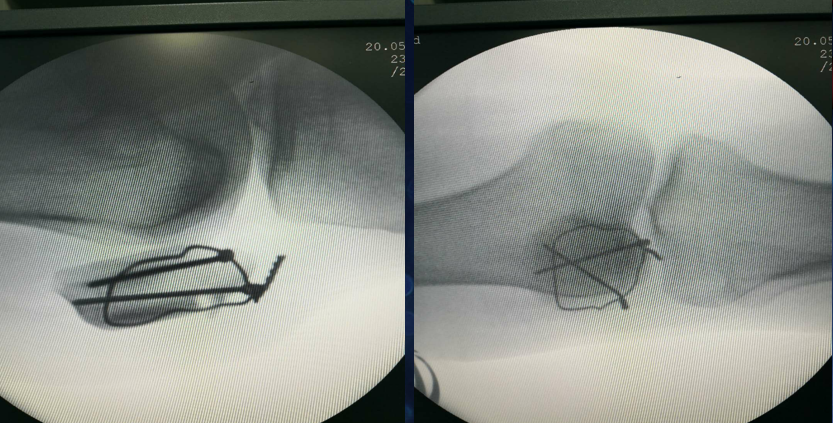

收紧钢丝打结使其骨折端复位,透视发现复位欠佳

继续收紧钢丝,骨折复位,剪断钢丝

将钢丝埋于深处

由下方两钢丝口打入两髌骨

术后复查